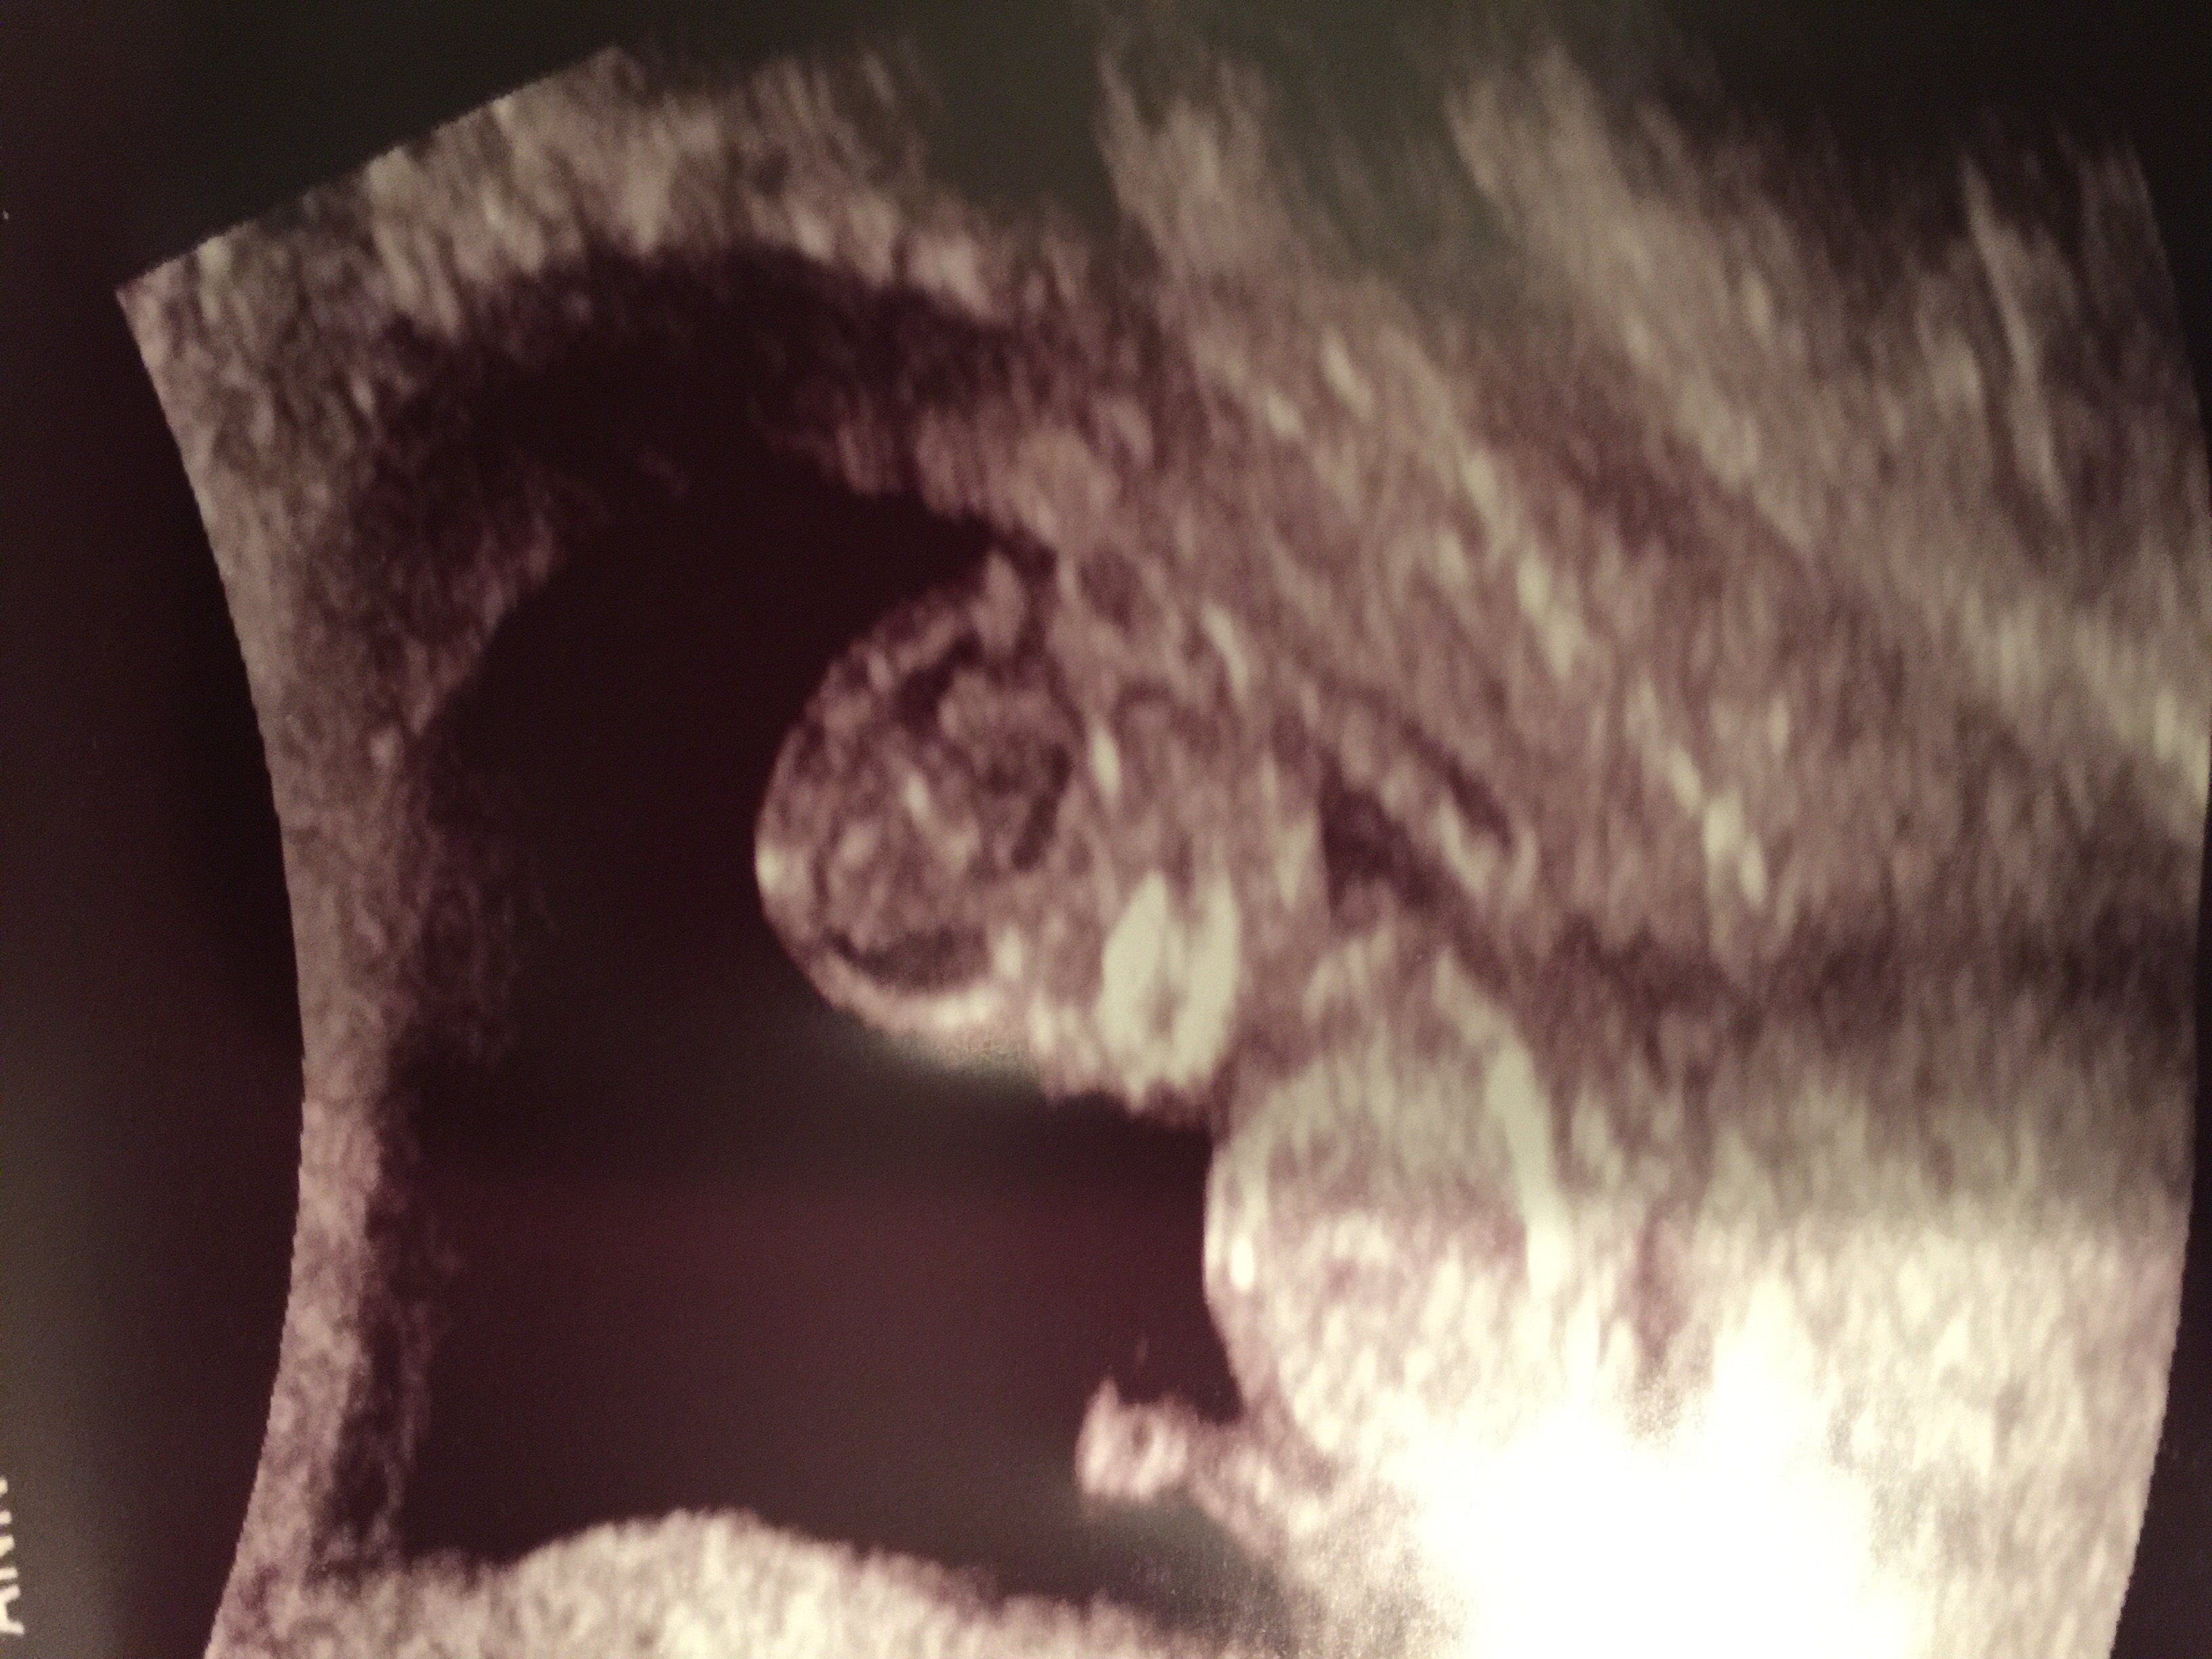

15w2d -- little boy is camera shy! He's laying with his arm curled under his face. His face resembles a Halloween mask! Lol super active with a heartbeat going from 144-151. Stretched out with his feet on one side, and head on the other.